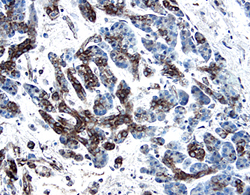

PDGF-C antibody in Human Pancreatic Cancer Tissue by Immunohistochemistry (IHC-P).

PDGF-C in Human Pancreatic Cancer Tissue.

PDGF-C was detected in immersion fixed paraffin-embedded sections of human pancreatic cancer tissue using 1.7 µg/mL Goat Anti-Human PDGF-C Antigen Affinity-purified Polyclonal Antibody (Catalog # AF1560) overnight at 4 °C. Tissue was stained with the Anti-Goat HRP-DAB Cell & Tissue Staining Kit (brown; Catalog # CTS008) and counterstained with hematoxylin (blue). View our protocol for Chromogenic IHC Staining of Paraffin-embedded Tissue Sections.